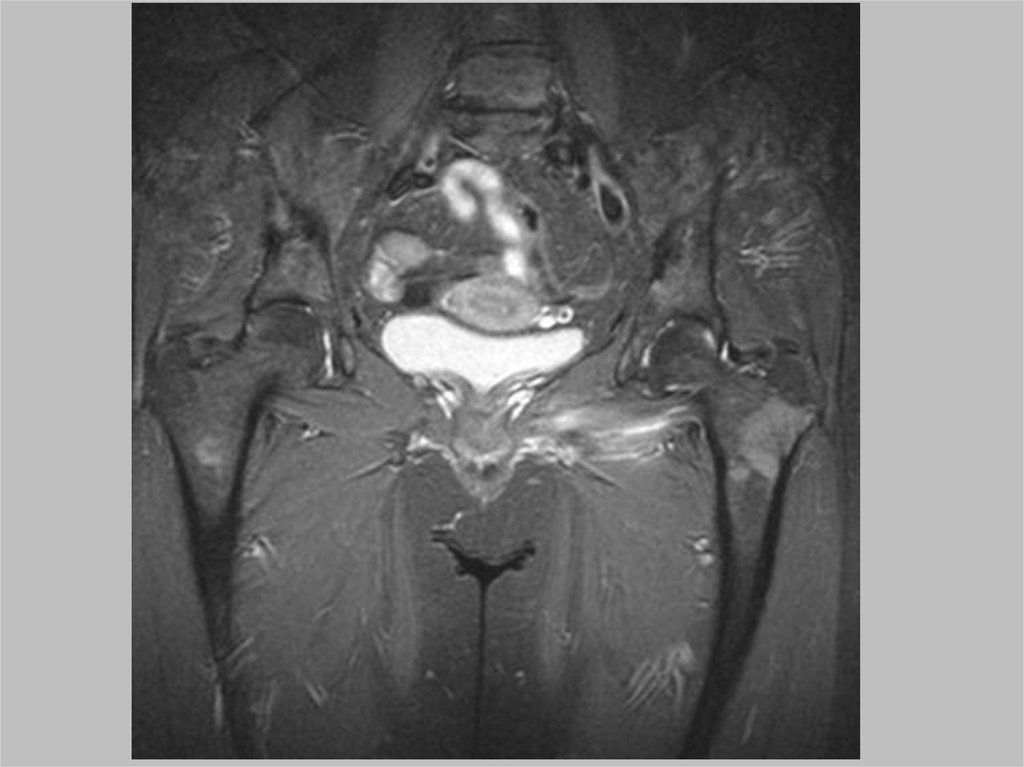

Воспалительные процессы

Бурситы

Илиотибиальный бурсит

Вертельный бурсит

52.

Септический артрит